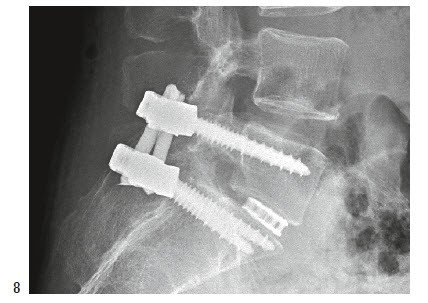

Liegt der Vorfall seitlich (lateral) zum Spinalkanal (bei rund 10 Prozent der Fälle), wird die Diskushernie von der Seite (lateral) entfernt, und zwar meist ohne Eröffnung des Spinalkanals. Liegt der Bandscheibenvorfall an geeigneter Stelle, kann er mit einer speziellen Optik und entsprechenden Instrumenten durch einen kleinen, lediglich ca. 1 cm langen Hautschnitt entfernt werden (Endoskopie).